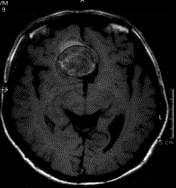

病历摘要:??患者男性,56岁,因右侧视力下降伴视野缺损2个月来院就诊,诉头痛,无明显头晕,无视物重影,无恶心呕吐,无肢体抽搐,无肢体乏力,胃纳佳,大小便...

问题 病历摘要:??患者男性,56岁,因右侧视力下降伴视野缺损2个月来院就诊,诉头痛,无明显头晕,无视物重影,无恶心呕吐,无肢体抽搐,无肢体乏力,胃纳佳,大小便正常,既往史无特殊,入院检查:神志清楚,言语清楚,体毛分布正常,左侧视力4.6,右侧视力4.0,粗侧右颞侧视野缺损,左侧正常,颈软,四肢肌张力正常,肌力正常,病理征(-)。 在巨型动脉瘤手术中,若术中需要夹闭载瘤动脉,下述那些方法可先预测夹闭后的效果可能是好的?提示:本例病患采用开颅手术治疗